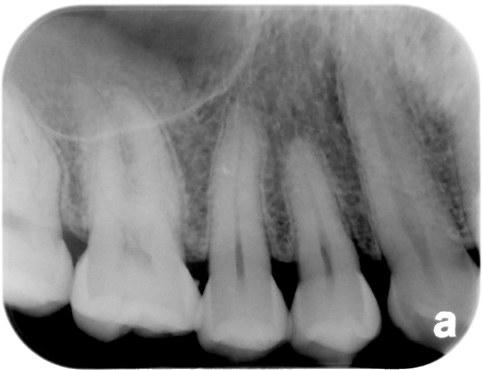

1. (Select ONE OR MORE correct answers)

The radiograph shows evidence of